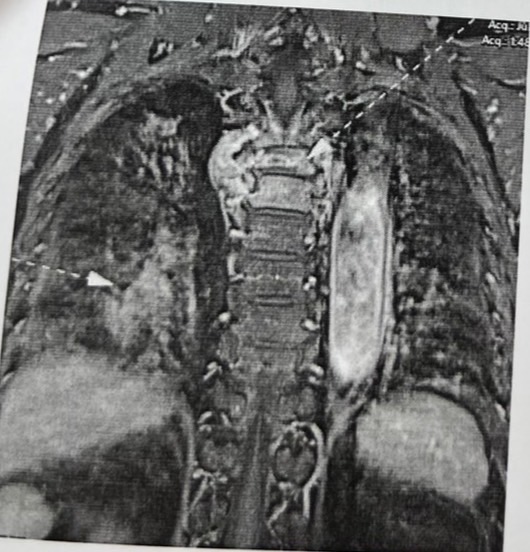

เมื่อต้นเดือนพ่อรู้สึกขาไม่ค่อยมีแรง ต้องใช้ไม้พยุง และหลังจากไปหาหมอ ตรวจโดยเข้าสแกน mri ผลออกมาแล้วพบก้อนในปอด

และก้อนที่กระดูกสันหลังทันเส้นประสาทใหญ่พอสมควร ทางรพ.จึงรีบส่งไปที่ศูนย์มะเร็งของจังหวัด

*ทางศูนย์มะเร็งเห็นผลตรวจ เลยให้ฉายแสงทันที 10 วัน และหมอแจ้งว่าเป็นมะเร็งระยะที่ 4 แล้ว และลามไปกระดูกสันหลัง

ลุกลามไปจุดอื่นด้วย โดยยังไม่ได้เจาะก้อนเนื้อตรวจ และมีนัด CT Scan อีกทีหลังฉายแสงค่ะ

ขอแนบรูปก้อนเนื้อที่พบนะคะ